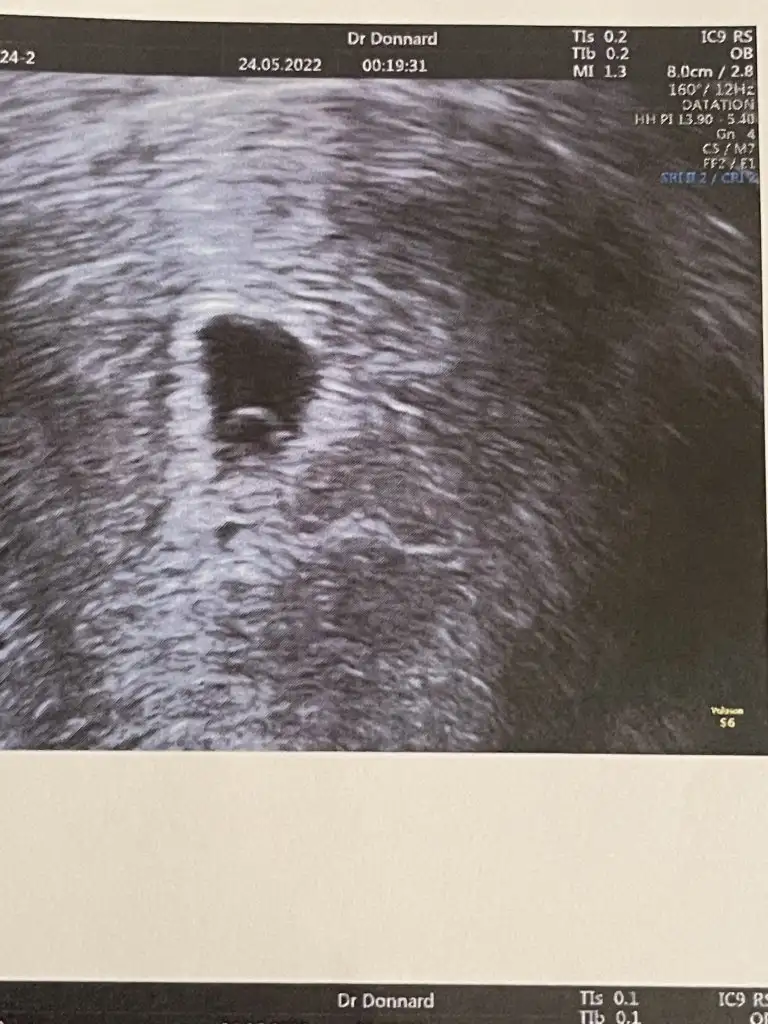

Benim içinde yorum yaparsanız sevinirim vajinal ultrason 6+3